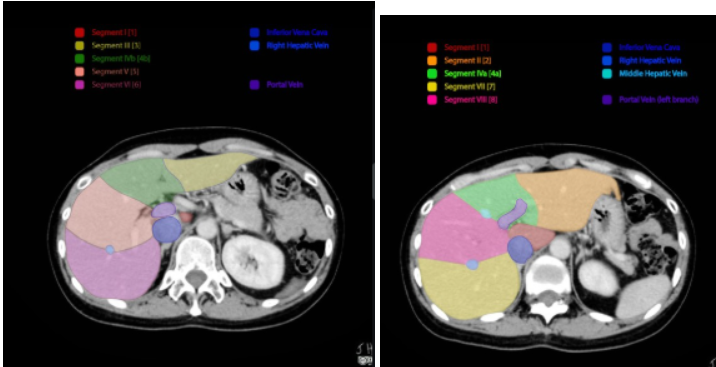

Qual estrutura define o lobo direito e esquerdo de acordo com a segmentação de Couinaud?

A veia supra-hepática média (linha de Cantlier).

O que diferencia os segmentos hepáticos inferior e superior?

A bifurcação da veia porta

Se eu vejo a bifurcação na TC, são os _______

inferiores

Setores hepáticos.

Setor lateral esquerdo: 2 e 3

Setor medial esquerdo: 4

Setor anterior direita: 5 e 8 (veia supra hepática direita que divide os setores a direita)

Setor posterior direito: 6 e 7

Hepatectomia maior x menor. Regrada.

Menores: até 2 segmentos hepáticos Maiores: >= 3 segmentos. Regrada: respeita a distribuição de Cuinaud.